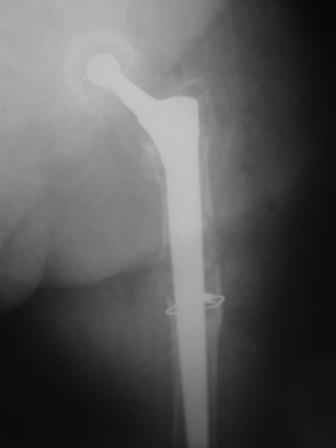

You transformed a cemented hip prosthesis to a cementless revision hip prosthesis with a little approach.

* your nail has a point of minus resistance at the tip of femural stem and at the fulcrum of the fracture; by the time could it break?

* by the time stem and nail could reciprocally move?

* distal fixation of the nail is based near only on two screws : are they sufficient to secure a good stability before fracture consolidation?

* materials of the stem and nail (I think Iron steel in both); if they should be different (and many hip prosthesis are made by an alloy that is not the same of the nails) we could see electrolytic phenomena

I generally should prefer a long stem revision prosthesis, as that allegated.